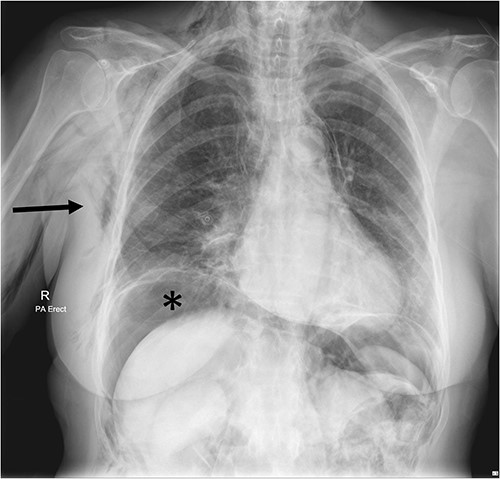

A chest X-ray confirmed subcutaneous emphysema and pneumoperitoneum and no pneumothorax (Fig. 1). Subsequent computed tomography (CT) of the abdomen and pelvis revealed extensive extraluminal gas throughout neck, torso and upper limbs including retroperitoneal, intraperitoneal, mediastinum, anterior and posterior chest wall, superficial and deep layers of the neck, right lower abdominal wall and bilateral inguinal canals (Figs 2 and 3).

Chest X-ray Day 2 post-operatively, showing extensive subcutaneous emphysema on the right (arrow) and subdiaphragmatic free gas (*) concerning for perforated viscus.